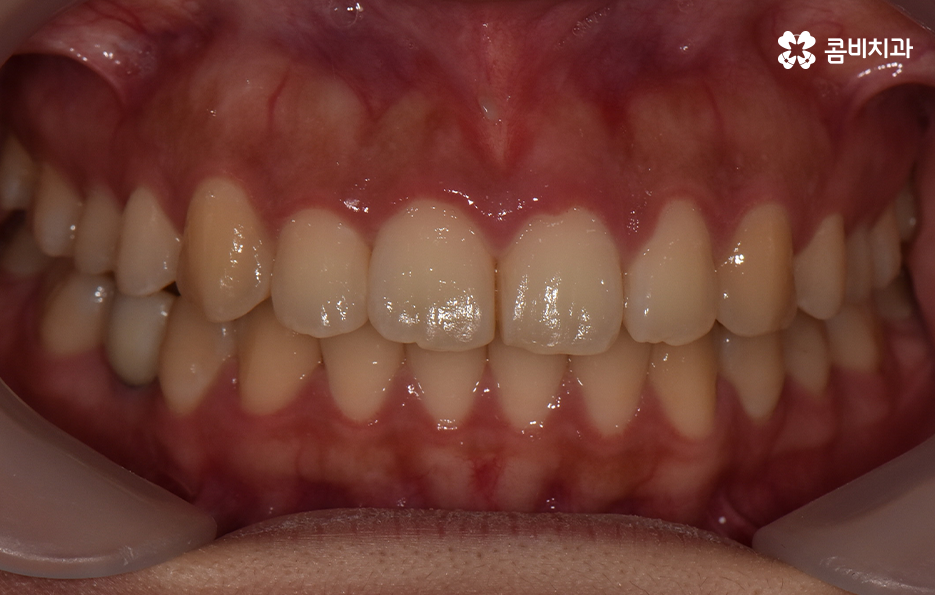

치아교정은 한 번 시작하면 중간에 쉽게 바꿀 수도 없고 어렵게 결심하는 만큼 장기적인 관점에서 치료 계획을 꼼꼼하게 세워야 할 필요가 있는데요. 덧니 발치 교정에 있어서도 단지 치열만이 아니라 치아교정 결과에 있어서 입술 라인과 얼굴형과의 조화까지 생각하고 당연히 교합도 잘 고려하여 발치 여부를 판단한다고 보시면 좋을 거예요

정리하면 덧니 발치 교정의 필요성은 각 개인에 따라 치료 계획은 천차만별이기 때문에 치과에서 정밀 검진과 함께 교정 전문의와의 충분한 상담을 통해서 판단해야 하며 보편적으로는 입술 라인을 고려하거나 돌출 등이 있어서 치열 뿐 아니라 입이 안쪽으로 들어가야 할 필요가 있다면 발치를 하는 것도 좋은 방법이 될 수 있어요

반대로 발치를 하는 것이 치료 결과에 좋지 않거나 덧니가 심하지 않은 경우에는 되도록 비발치로 교정을 진행하는 경우도 있다는 점도 알아두시면 좋을 거예요. 치아교정은 치열만 고려하여 치료 계획을 세우지 않고 결과에 대해 고려하여 계획하는 만큼 치료 뿐 아니라 유지관리까지 오랫동안 믿고 찾을 치과를 선택해야 하며 무엇보다 자신에게 적합한 치료 계획을 잘 세워보시길 바라고 있어요